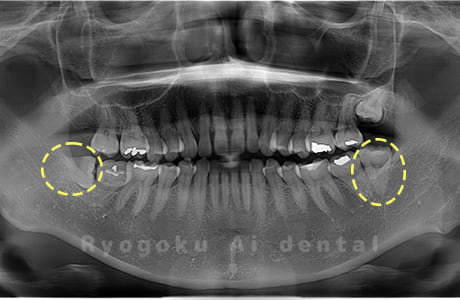

Case08

- 下顎の水平埋伏智歯2本

- 治療内容

- 下顎の水平埋伏智歯2本を抜歯したケースです。

<リスク・副作用>

手術後は痛み、腫れ、痺れなどの副作用が生じる場合があります。